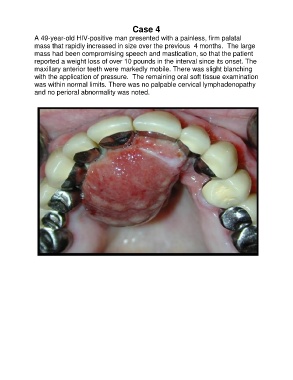

Case 4

A 49-year-old HIV-positive man presented with a painless, firm palatal

mass that rapidly increased in size over the previous 4 months. The large

mass had been compromising speech and mastication, so that the patient

reported a weight loss of over 10 pounds in the interval since its onset. The

maxillary anterior teeth were markedly mobile. There was slight blanching

with the application of pressure. The remaining oral soft tissue examination

was within normal limits. There was no palpable cervical lymphadenopathy

and no perioral abnormality was noted.